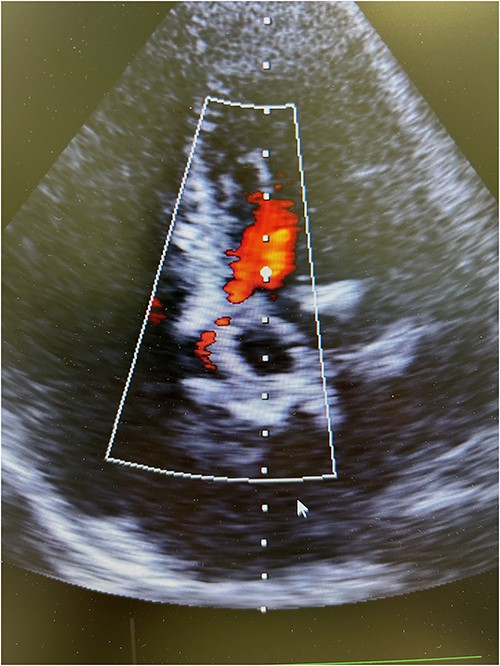

The patient experienced significant dyspnea, increased passiveness, decreased performance, and cardiac echocardiography revealed a destroyed, regurgitant, and stenotic aortic valve prosthesis with myocardial calcification of the left outflow track (Fig. 1) including a peak mean aortic gradient of 76/49 mmHg, Vmax 4.3 m/s and AVA 1.0 cm2 and significant regurgitation (Fig. 2). Minimal mitral valve regurgitation and some coronary artery stenosis were also present.

Preoperative transesophageal echocardiography showing significant regurgitation and stenosis of the aortic valve bioprosthesis.